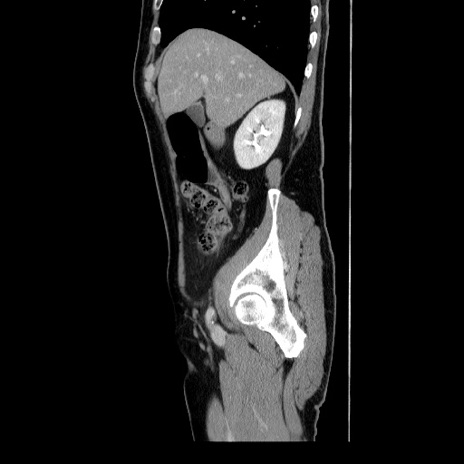

症例34(矢状断像)

【症例】60歳代 男性

【主訴】右鼠径部膨隆

【現病歴】1年程前より右鼠径部膨隆あり。自己にて還納可能だったため放置していた。3時間前より右鼠径部の脱出を認め、還納困難となり受診。

【既往歴】高血圧

【身体所見】右鼠径部に小児頭大の膨隆あり。弾性硬であり、用手還納は困難。左鼠径部にも膨隆を認める。脱出はなし。